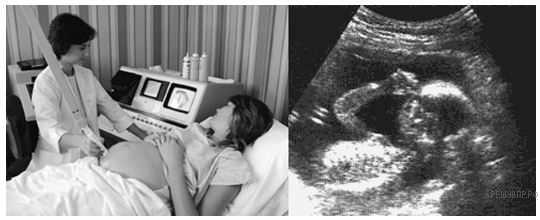

Чтобы со­здать изоб­ра­же­ние плода уль­тра­зву­ко­вой ап­па­рат дол­жен вы­чис­лить рас­сто­я­ние между пло­дом и дат­чи­ком. Уль­тра­зву­ко­вые волны рас­про­стра­ня­ют­ся в брюш­ной по­ло­сти со ско­ро­стью 1540 м/с. Что дол­жен из­ме­рить уль­тра­зву­ко­вой ап­па­рат, чтобы вы­чис­лить рас­сто­я­ние между пло­дом и дат­чи­ком?

Решения заданий с развернутым ответом не проверяются автоматически. Запишите решение на бумаге.

На следующей странице вам будет предложено проверить их самостоятельно.

17

Тип Д17 № 434

i

Развернуть

Что можно опре­де­лить уль­тра­зву­ко­вым об­сле­до­ва­ни­ем бу­ду­щей ма­те­ри о ре­бен­ке? В от­ве­те за­пол­ни­те про­пуск в пред­ло­же­нии «_________ детей, а также их ________». За­пи­ши­те его без про­бе­лов и иных до­пол­ни­тель­ных сим­во­лов.

Ответ:

18

Тип Д18 C9 № 435

Изоб­ра­же­ние плода может быть также по­лу­че­но с по­мо­щью ис­поль­зо­ва­ния рент­ге­нов­ских лучей. Од­на­ко жен­щи­нам во время бе­ре­мен­но­сти ре­ко­мен­ду­ет­ся из­бе­гать ис­сле­до­ва­ния брюш­ной по­ло­сти рент­ге­нов­ски­ми лу­ча­ми. По­че­му жен­щи­не во время бе­ре­мен­но­сти сле­ду­ет из­бе­гать ис­сле­до­ва­ния брюш­ной по­ло­сти рент­ге­нов­ски­ми лу­ча­ми?